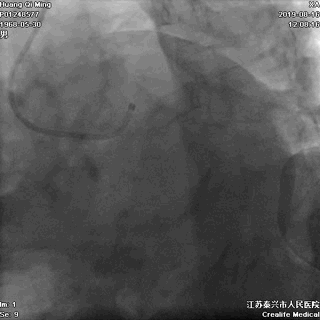

LCX PCI过程

手术器械:

7F EBU3.5

0.014” Runthrough NS

2.0*20 Maverick 球囊

2.75*23 DES

2.75*12 Quantum Maverick 球囊

3.0*8 Quantum Maverick 球囊

导丝通过病变

球囊扩张,PTCA

支架定位和植入

高压扩张使支架贴壁

LCX植入后即刻效果满意